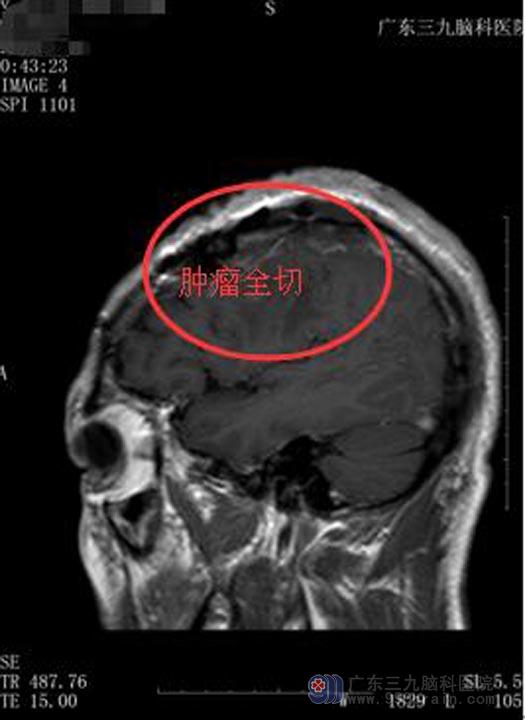

家属同意行“左侧额部脑膜瘤切除术”。术中见肿瘤明显侵犯脑膜,边界较轻,血供丰富,显微镜下整块全切肿瘤。术后张先生康复很快,已满意出院。

手术后